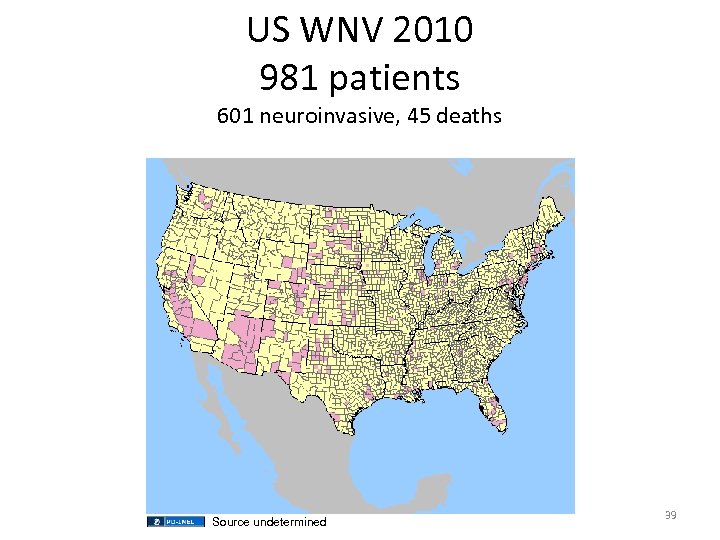

US WNV 2010 981 patients 601 neuroinvasive, 45 deaths Source undetermined 39